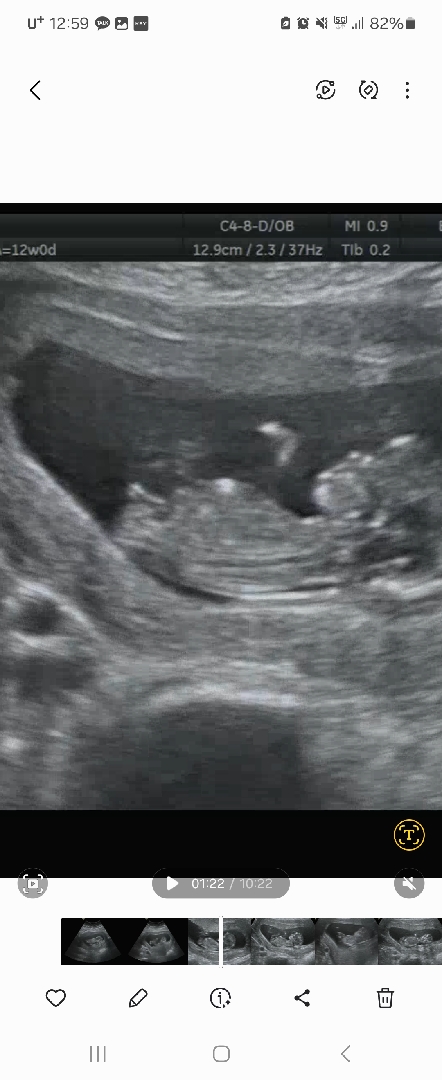

12주차 0일 때 찍은 우리 열무 사진이에요~ 저는 아무리 봐도 잘 모르겠어서 ㅠㅠ 보시기에 어떤지 다들 한번씩 봐주세요~~